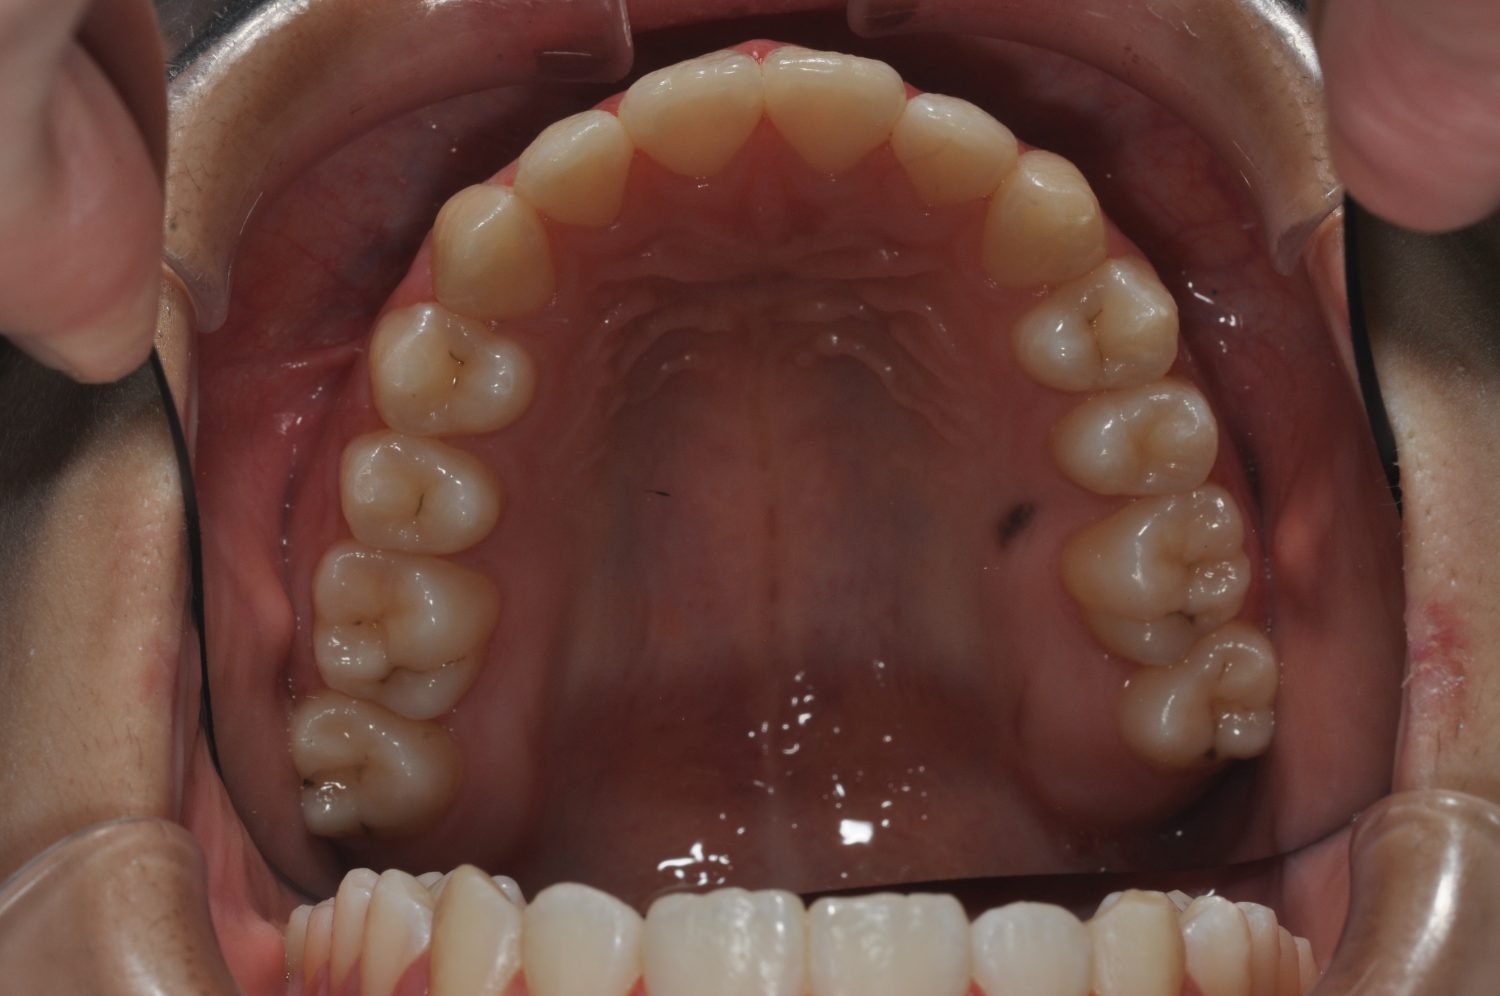

| 主訴 | 前歯部の叢生と正中の不一致 |

| 治療内容 | 軽度の叢生の改善を行うために、非抜歯でのマルチブラケット装置による治療を行った。 |

| 治療費 | Ⅱ期治療費:275,000円(税込) 調整料 5,500円(税込)×18回 保定時:22,000円(税込) 計 396,000円(税込) |

| 治療期間 | 2年2ヶ月 |

| 治療回数 | 20回 |

| 想定されたリスク | 矯正後に後戻りする可能性がありました。 |

Ⅰ期治療で叢生、反対咬合の改善をセクショナルアーチとMPAを使用して改善した後、成長観察を行っていました。永久歯の萌出したため、Ⅱ期治療を開始することとなった。上下顎とも骨格的に問題がなかったため、非抜歯で治療を行った。